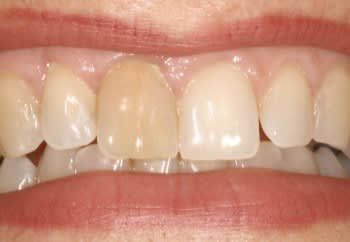

Ci joint cas avec membrane résorbable laissée exposée volontairement ( technique Bio coll proposée par Anthony G. Scar dans les années 2000 remis au gout du jour par tarnow en 2006 ).

Celà ne marche pas avec toutes les membranes...

fig 6 réouverture J0 + 6mois

fig 7 vue clinique J0 + 2ans ( Prothèse Dr G.D 31 )

fig 8 vue clinique JO + 5ans (léger décalage des collets entre 11 et 21 comme à l'origine)

fig1 avant

fig2 aprés.